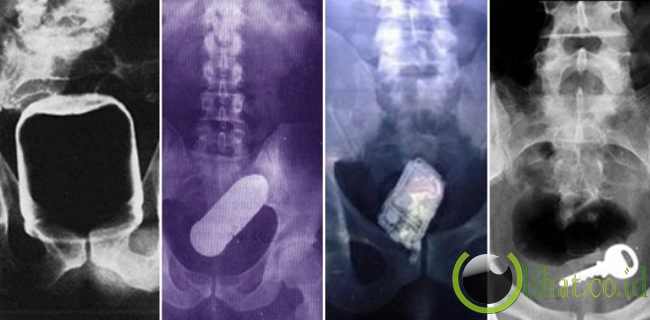

[lihat.co.id] - Pernahkah Anda membayangkan sebuah benda aneh tersangkut di tubuh Anda? Jika belum, beberapa orang di belahan dunia pernah mengalaminya.

Barang-barang itu bisa jadi hanya barang-barang sederhana di rumah, seperti sebuah kunci maupun stoples kacang. Namun sayangnya, barang-barang ini tentu mengganggu dan bisa jadi mengancam kehidupan Anda.

1. Sebuah Kunci

[lihat.co.id] - Sudah mencari kunci mobil ke mana-mana tapi masih juga belum ketemu? Mungkin saja tersangkut di dalam tubuh Anda.

Kunci ini misalnya, tersangkut di tubuh manusia. Tentu saja, para dokter yang melihatnya juga terkejut.

2. Vibrator & Penjepit Salad?

[lihat.co.id] - Tak perlu detektif untuk mendeteksi penyebab 'kasus' ini. Vibrator tersangkut di tubuh pria ini sebenarnya sudah cukup untuk memasukkan pria ini ke rumah sakit. Namun yang lebih parah, saat ia mencoba mengambil vibrator ini dengan penjepit salad, penjepit itu ikut tertinggal...

3. Amunisi Rawan Meledak!

[lihat.co.id] - Veteran perang dunia kedua yang berasal dari London ini sebelumnya menderita karena penyakit hemorrhoids. Ia biasanya menggunakan senjatanya untuk mendorong hemorrhoids-nya ke rectum.

Suatu hari, ia mendorong terlalu jauh dan... amunisi ini tertinggal di anusnya. Yang berbahaya, amunisi ini masih hidup dan dapat meledak sewaktu-waktu.

4. Stoples Selai Kacang

[lihat.co.id] - Entah bagaimana barang yang satu ini bisa tersangkut di dalam tubuhnya. Stoples selai kacang ini secara mengejutkan terfoto lewat X-Ray.

5. Botol Parfum

[lihat.co.id] - Seorang pengacara berusia 39 tahun masuk ke rumah sakit gara-gara sebuah botol parfum tersangkut di anusnya. Ini bukan pertama kalinya ia memasukkan benda ini, namun kali ini, barang ini tersangkut. Ouch!

6. Handphone Berdering!

[lihat.co.id] - Pengacara dari Georgia mandi dengan membawa handphone-nya. Masalahnya, saat ia terpeleset dan jatuh, hingga handphone-nya tersangkut dalam tubuhnya. Saat operasi pengambilan handphone tersebut, benda itu berdering tiga kali.

7. Sebuah Gelas

[lihat.co.id] - Daripada berpikir bagaimana cara mengeluarkan gelas ini, mungkin Anda lebih penasaran bagaimana cara memasukkannya.

8. Lampu Senter

[lihat.co.id] - Entahlah apa yang terjadi hingga lampu senter ini bisa masuk ke dalam tubuhnya. Takut gelap?

9. Mobil Mainan

[lihat.co.id] - Kejadian ini bukan kecelakaan, namun disengaja. Ryan Dunn dari reality show Jackass, secara sengaja memasukkan mobil mainan hanya untuk mengerjai pihak Unit Gawat Darurat.

10. Semen Membeku

[lihat.co.id] - Cerita yang ini sangat aneh. Cairan semen sengaja dimasukkan awalnya hanya untuk bermain-main. Namun sayangnya, secara natural, semen itu membeku. Butuh operasi untuk mengeluarkannya.